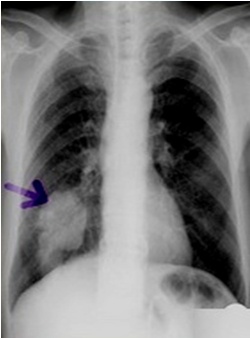

图中可见右下肺分叶状肿块,根据公式诊断周围型肺癌